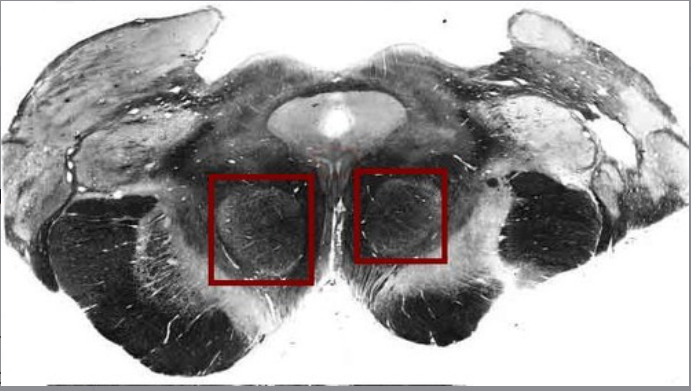

substantia nigra

located: midbrain

fxn: produces DOPAMINE (motor, cognition, behavior)

red nucleus

fxn: coordination of sensorimotor info + rubrospinal tract